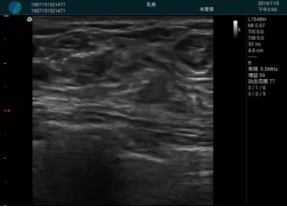

清晰顯示孕囊,通過軟件包計算孕齡7w+6d

M20實時引導,術(shù)中清晰顯示孕囊被破壞和抽吸針的過程,清晰顯示吸引針

抽吸結(jié)束后縱切子宮,孕囊已被完全抽吸,未見明顯殘留

橫切子宮,發(fā)現(xiàn)右側(cè)宮腔靠近宮角處有少許脫模樣殘留

M20引導下,抽吸針找到右側(cè)宮角處再次清掃

二次抽吸后再次進行超聲檢查,宮腔未見殘留,宮腔線清晰顯示